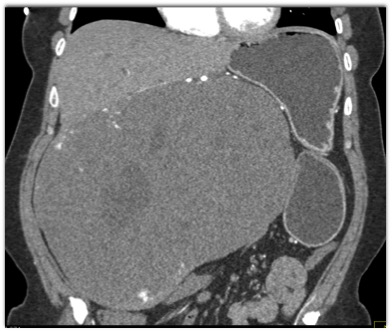

The best diagnosis for this hepatic mass is?

hepatoma

cholangiocarcinoma

hemangioma

FNH